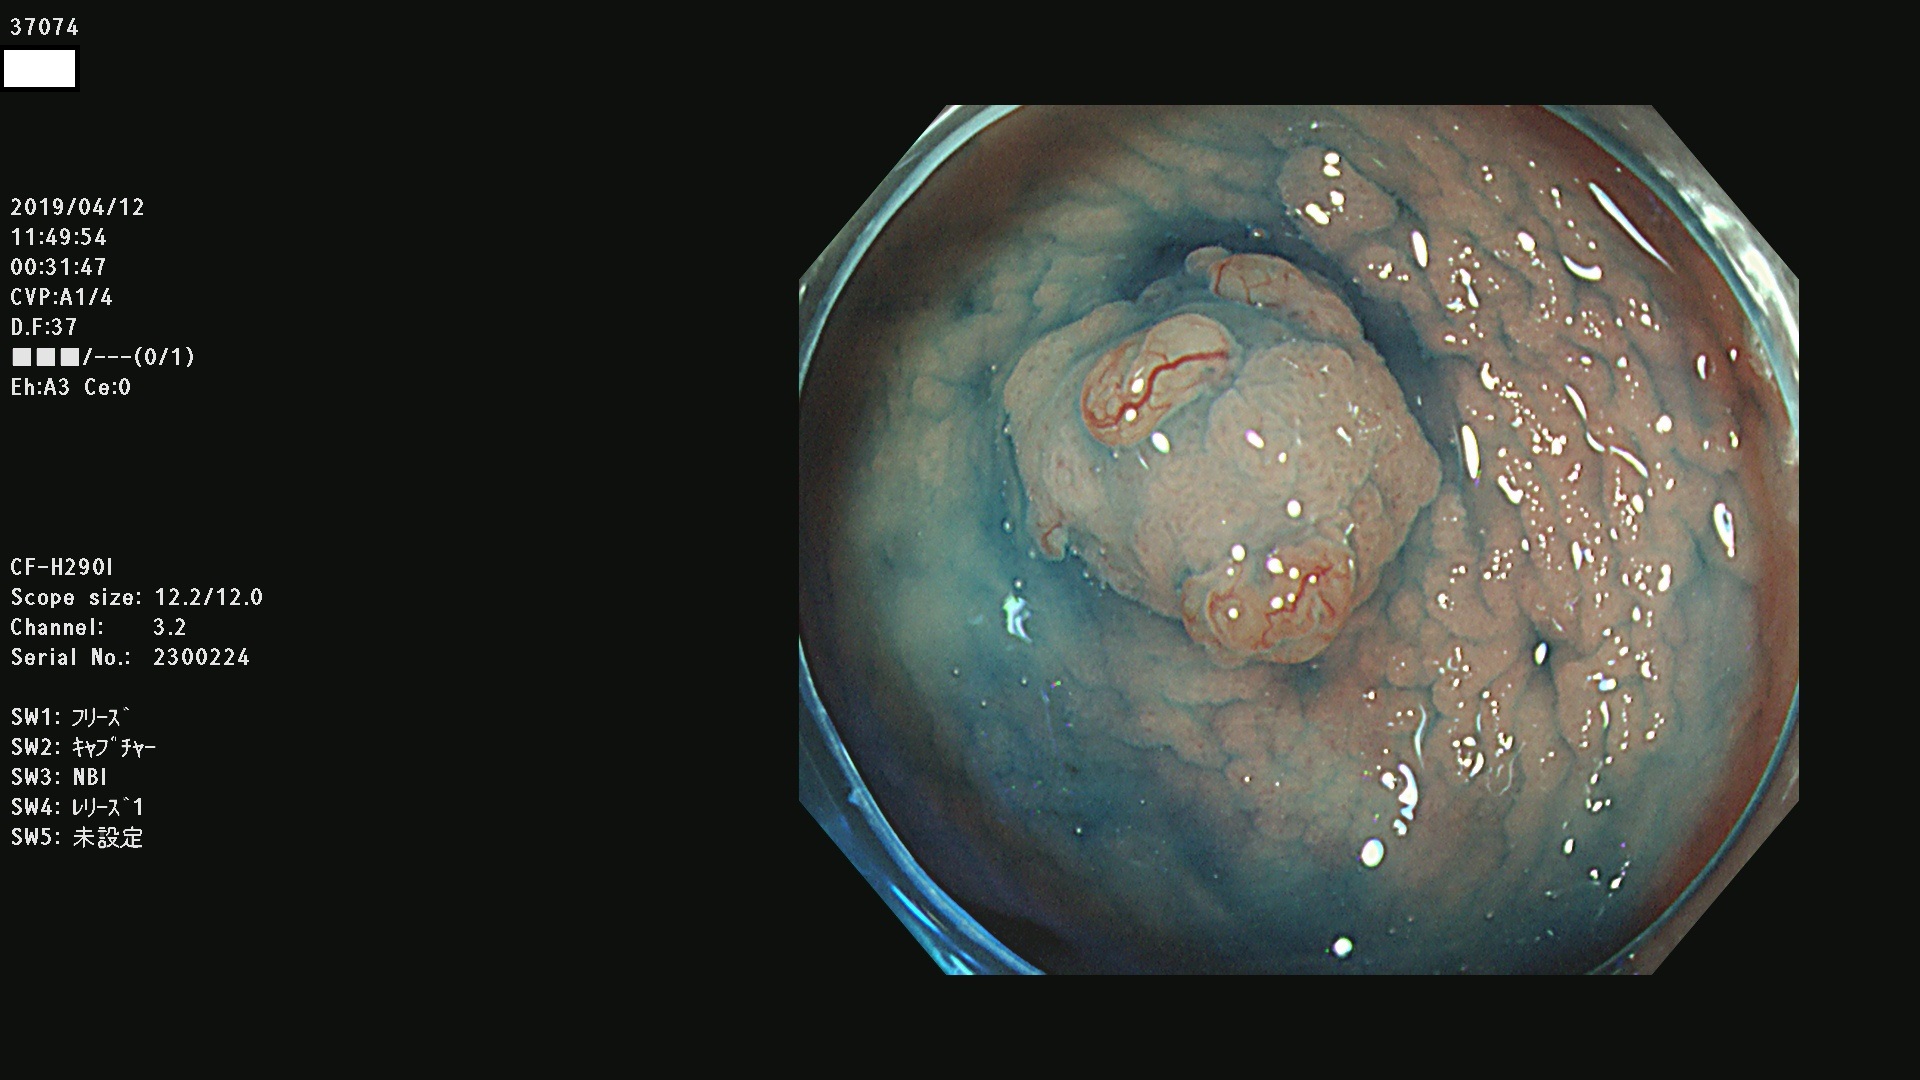

37000 37002 37004 37005 37006(SSAPのみ) 37007 37009 37013 37014 37015 37017(SSAPのみ) 37019 37020 37021 37022 37025 37026 37027 37028 37029 37031 37032 37033 37034 37035 37036 37037 37038 37041 37042 37043 37044 37045 37047 37051 37052 37053(SSAPのみ) 37055 37056 37058 37060 37061 37062 37063 37067 37072 37073 37074 37076 37077 37078 37079 37080 37081 37083 37084 37085(SSAPのみ) 37086 37087 37088 37089 37092 37093 37094 37095 37097 37098 3709

発見困難で危険性の高い平坦型病変(上記100名より抽出)